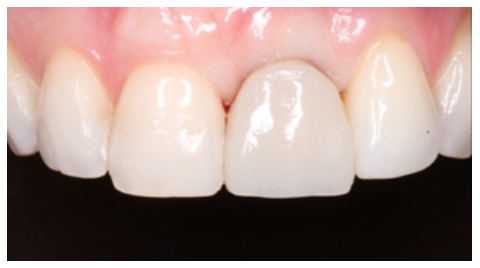

Given the good evolution at 6 months, the position of the OII and the emergence profile were recorded via an individualised transfer to replicate the gingival architecture faithfully and in detail (Figures 26 and 27). The final fixed prosthesis screwed to the OII was inserted 7 months after the treatment had started (Figures 28 and 29).